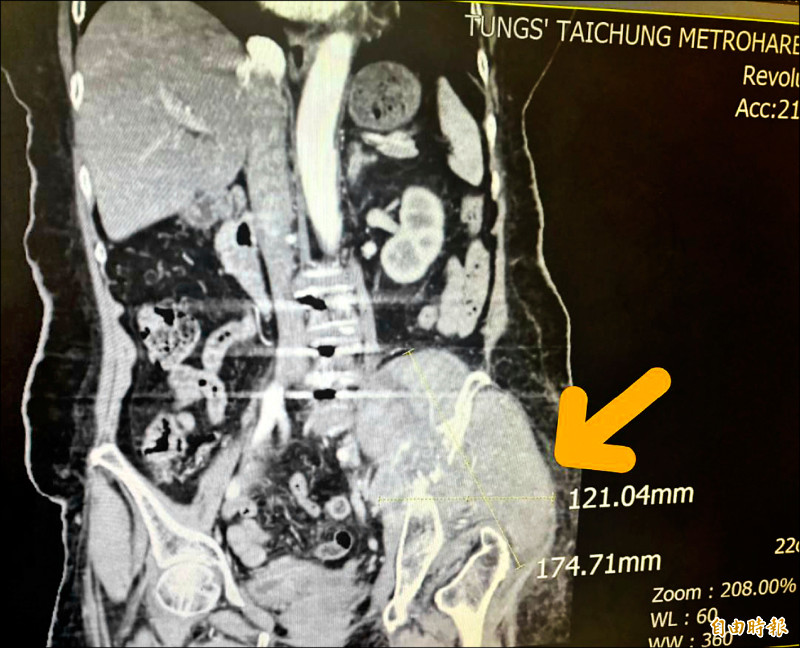

由於張婦的腫瘤細胞太大(約12.1公分×17.4公分),且腫瘤位置執行手術風險過高,葉啟源採用銳視刀適應性放射治療,利用空間分割點狀治療方式,局部給予點狀高劑量的放射線,以高劑量消融巨大、抗放射性腫瘤,再配合傳統銳視刀,即以傳統劑量梯度保護周圍的健康組織與器官,經過1個月26次治療後,腫瘤縮小至9.8公分×10.1公分,緩解骶叢神經受壓迫的情況,患者疼痛及行動能力明顯改善。